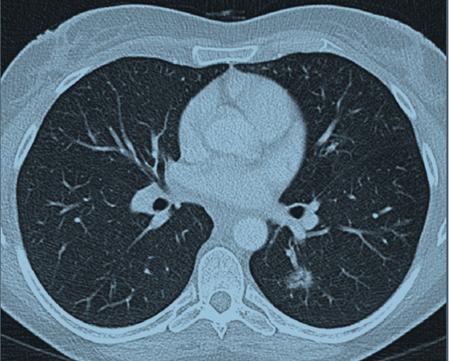

The patient’s routine chest X-ray was normal. Computed tomography (CT) scan of the chest revealed a focal ill-defined alveolar opacity in the peribronchial region of the left lower lobe apical segment and another smaller similar opacity in the left upper lobe centrally (Figure 1). Computed tomography scan of the sinuses (Figure 2) showed near complete opacification of the frontal and the visualized ethmoid sinuses with mild mucosal thickening throughout the maxillary, sphenoid, and ethmoid sinuses and hypertrophy of the turbinates.

Figure 2: Computed tomography scan of the sinuses showing near complete opacification of the frontal and the visualized ethmoid sinuses.